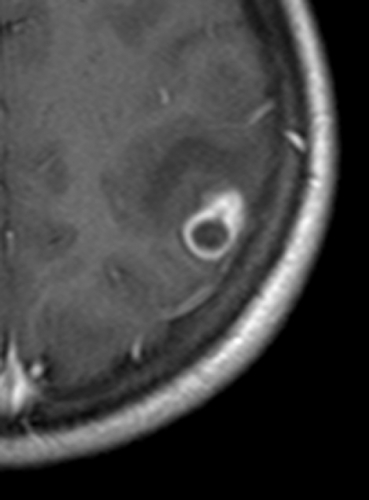

Beslut fattades om neurokirurgisk exstirpation av lesionen. Operatören beskrev en spelkulestor, hård och välavgränsad förändring samt en påtaglig reaktion i hinnorna. Histopatologisk undersökning av förändringen visade en solitär, välavgränsad process (8 6 mm i snittytan) med en bred, fibrös kapsel och runt den en uttalad infiltration av inflammatoriska celler, främst plasmaceller och eosinofila leukocyter. I det nekrotiska cystinnehållet urskildes cystvägg och en central skolex (huvud) stadd i nedbrytning (Figur 3 och Figur 4), således ett för neurocysticerkos diagnostiskt fynd.